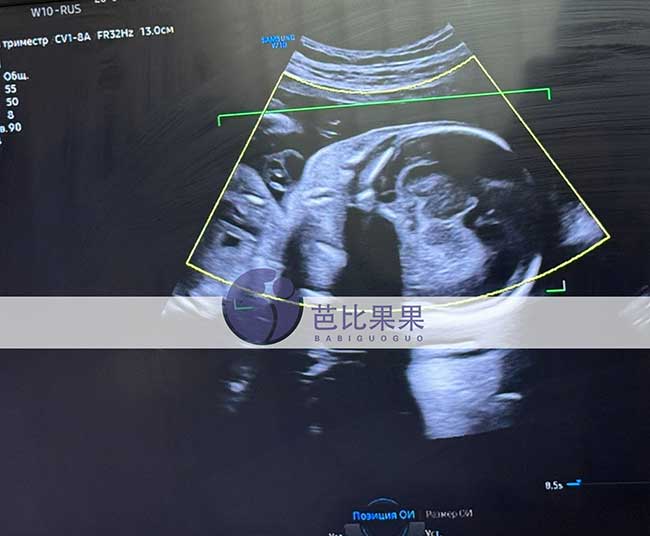

吴先生到乌克兰匹配的试管妈妈如期来做四维彩超啦!胎宝宝各项发育指标都稳稳达标,健健康康茁壮成长,每一次产检都是满心欢喜,静待可爱小天使平安到来。

吴先生到乌克兰匹配的试管妈妈如期来做四维彩超